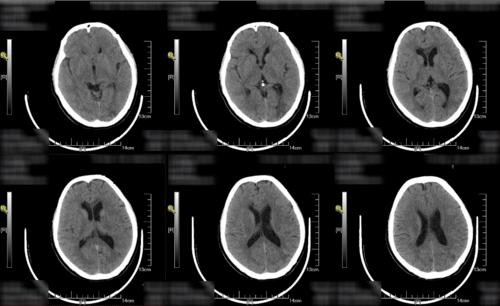

颅内多发梗塞灶是什么意思

脑部多发性缺血,梗塞灶。软化灶

多发腔梗灶释义.诊疗

多发性腔梗就是多发性腔隙性脑梗塞,属于脑梗塞的一种特殊类型,多发生在基底节区。是在高血压、动脉梗化的基础上,脑深部的微小动脉发生闭塞,引起脑...

多发性脑腔隙灶是什么意思?

多发性腔隙灶是指脑内有多个小的梗死灶,一般是因为高血压和糖尿病引起的,可能会出现纯感觉障碍,也可以出现纯运动功能障碍。患者平常一定要多注意休息,不要熬...

双侧额顶叶皮层下放射冠区半卵圆中心区多发缺血梗塞灶_千问健康

您的检查结果提示您是是脑动脉硬化、脑供血不足,建议积极药物治疗,防止脑血管事件。意见建议:1、建议口服尼莫地平、西比灵扩张脑血管、改善脑供血...

查体,发现脑内多发缺血梗塞灶-99健康问问

问题分析:根据你说的情况,患者属于多发性脑梗塞的表现,引起的原因可能是由于脑血管硬化,导致脑血管狭窄和痉挛,在一些诱因的作用下引起疾病的发生。...

什么叫多发性脑梗塞

多发性脑梗塞多发生在老年人身上,老年人由于各个器官的老化经常会导致很多的疾病,比如说老年痴呆、帕金森综合症和癫痫等等,这些对于老年人的生活影...

脑内多发缺血梗死灶空蝶鞍是什么病

脑内多发缺血梗死灶空蝶鞍是多发性缺血性梗死,空蝶鞍是没有必要处理的,因此需要针对脑缺血进行一步的进行治疗。多发性脑缺血说明脑血管有动脉硬化...

双侧额叶梗塞灶是什意思

问题分析:您好,根据您的描述,您的情况可能是由于脑梗塞。由于脑动脉粥样硬化,血管内膜损伤使脑动脉管腔狭窄,局部血栓形成动脉狭窄加重或完全闭塞...

脑内多发空梗是什么意思?

脑内多发腔梗,就是说明脑内多处部位发生了小的血管的梗塞,一般是深穿支的血管。如果反复发生梗塞,患者会出现腔隙状态的症状,会出现饮水呛咳,吞咽困难,恶心...